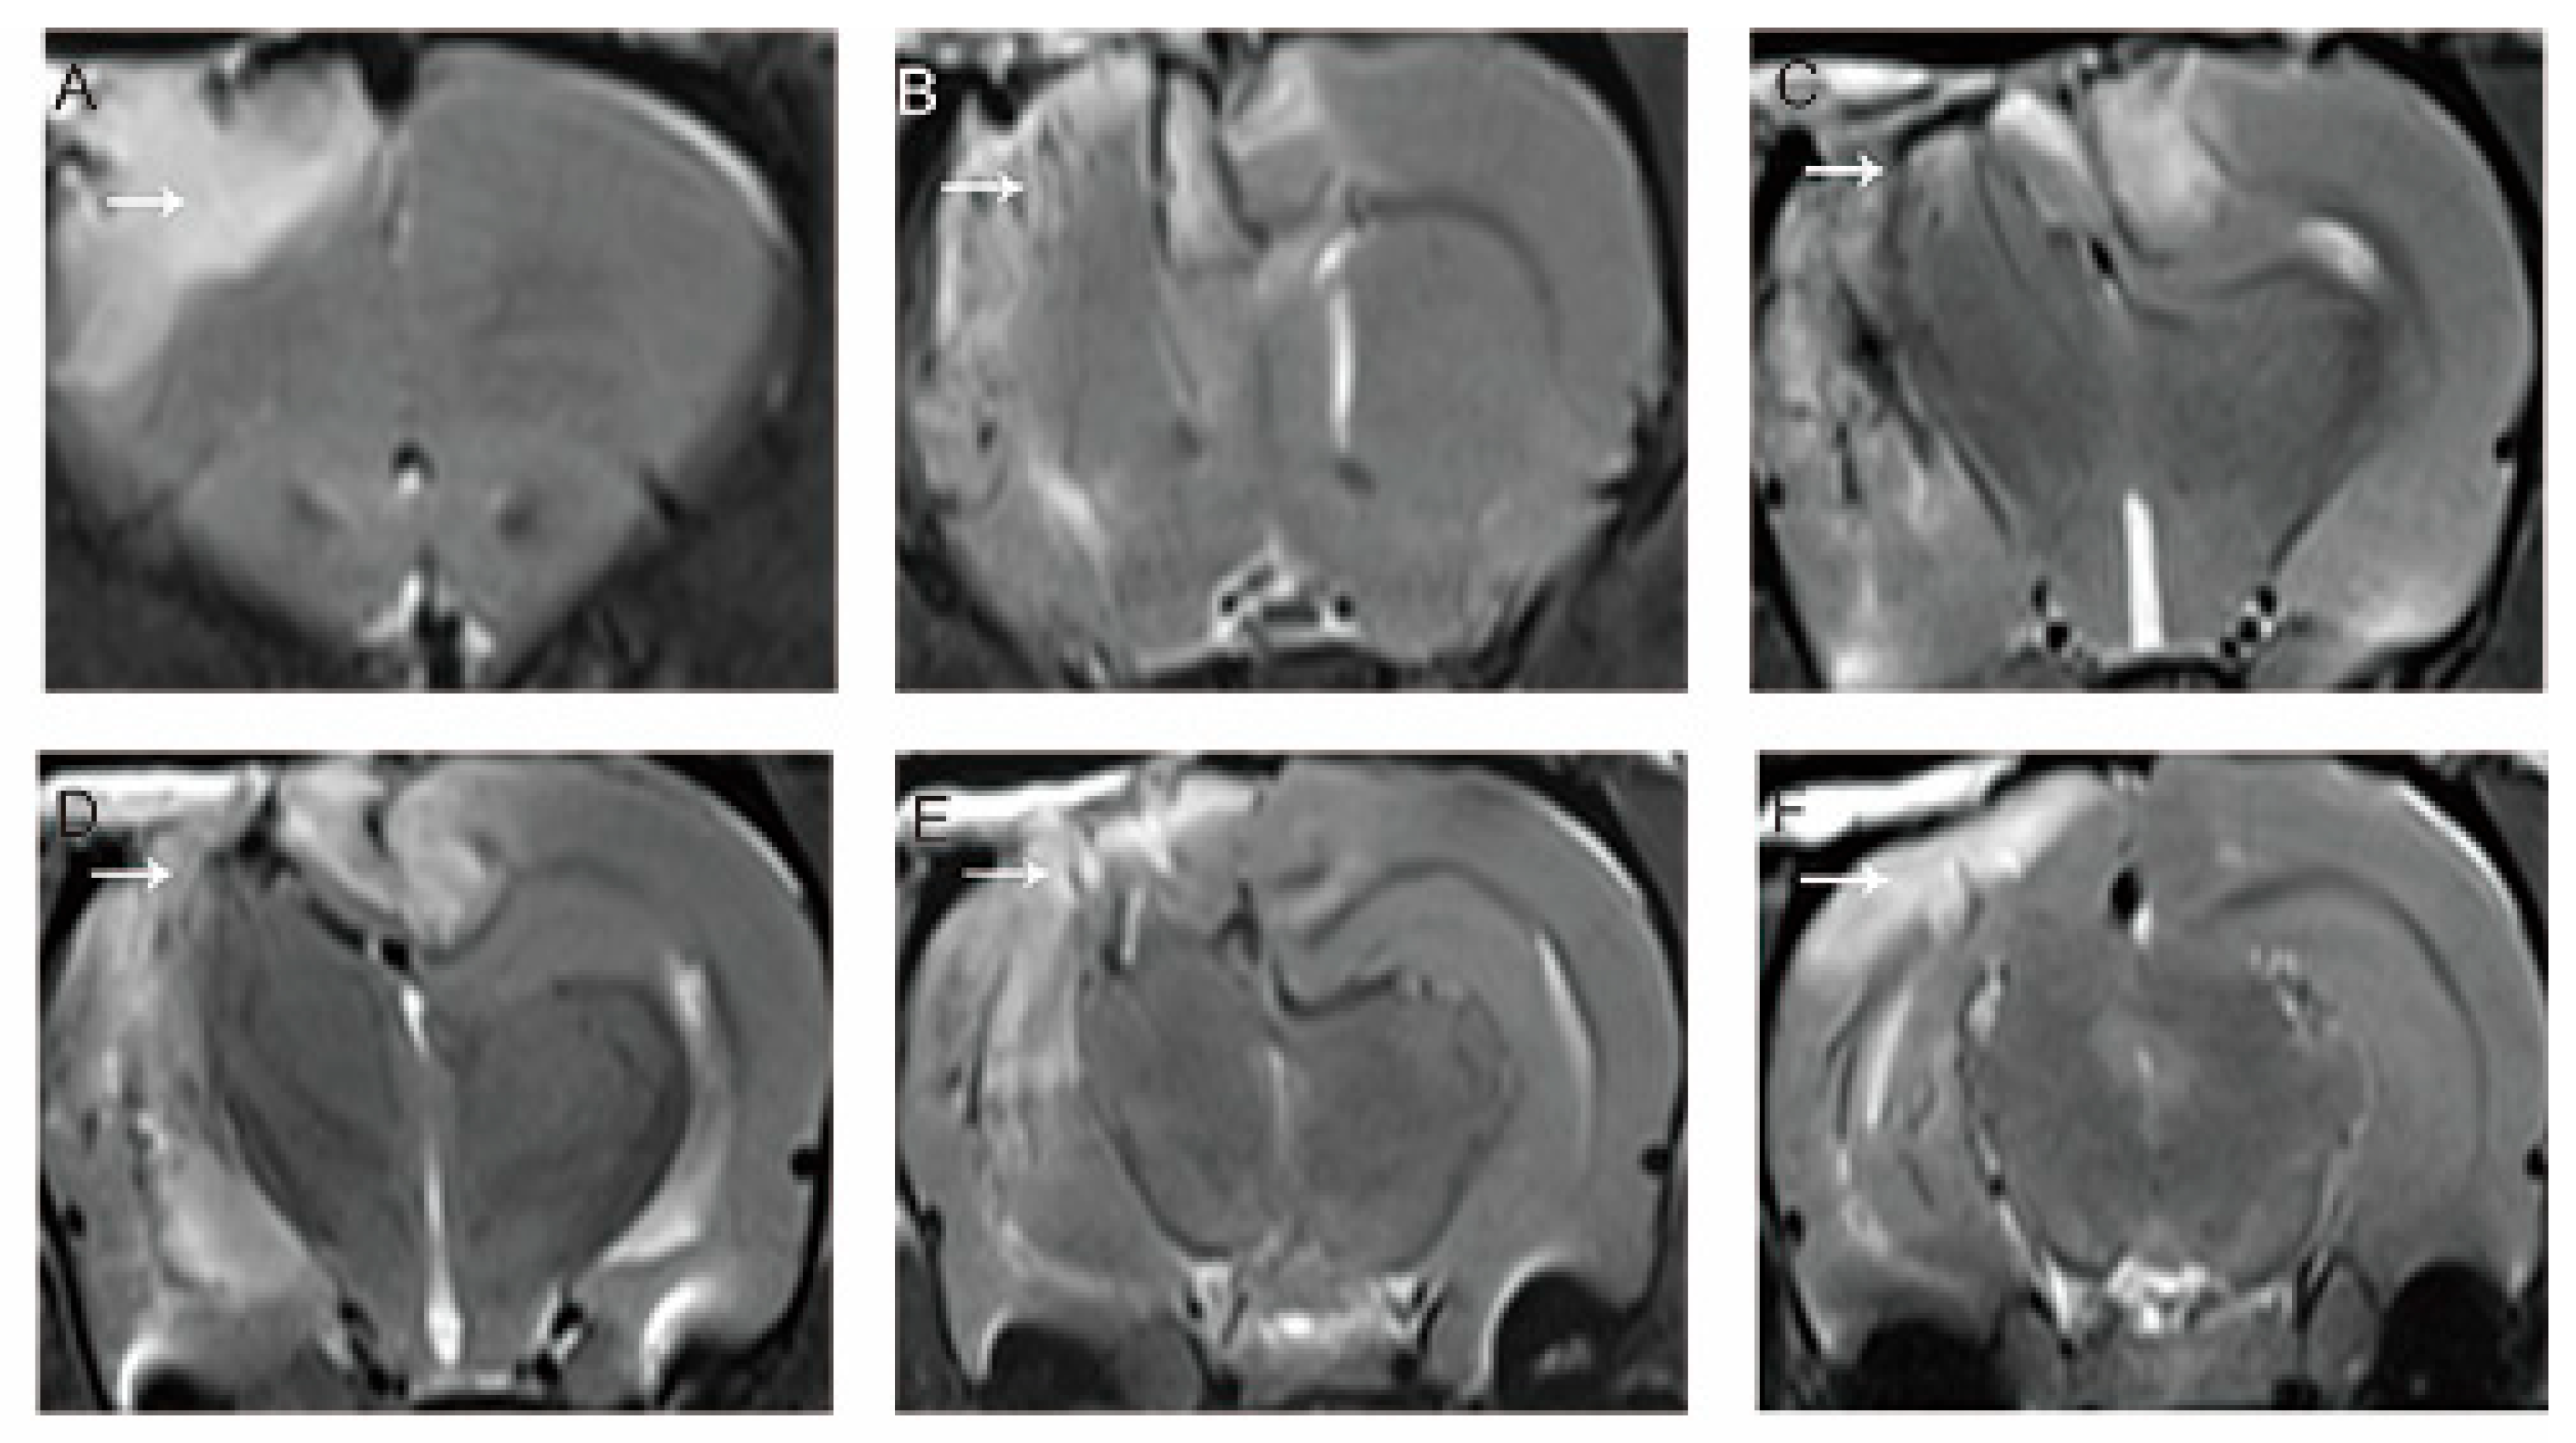

3.1. MRI Evaluation of the Model